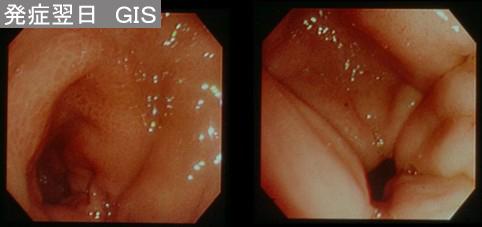

A case of gastric inflammatory disease which was suspected to be phlegmonous.

Saga Pref., Saga University Hospital (Saga University Hospital)

60-64

염증성 및 궤양성질환/기타

위(부위)/2개 이상

내시경